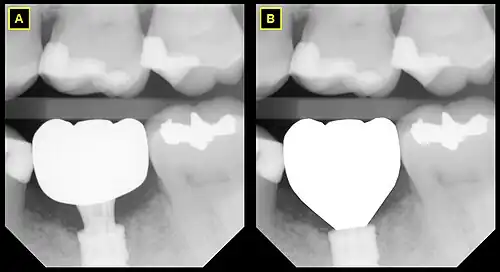

A This radiograph demonstrates an emergence profile that ignores the gingival tissue, generally presenting clinically with black triangles and food traps on either side of the implant. The crown (white) emerges supragingivally and does not take advantage of the available running room of 3mm. Instead, a 3mm ti-base was used.

B This emergence profile respects the gingival architecture and emerges fully subgingivally.